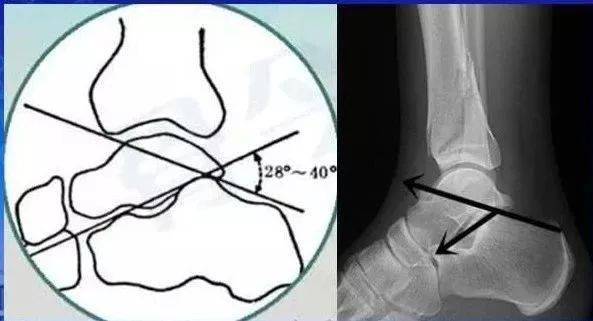

侧位片 bohler角:前突最高点,后关节面的最高点的 连线与后关节面的

跟骨两个角度:bohler′s角(以跟骨后关节面后上缘为顶点,分别连接骰骨

8cm; 3,跟骨倾斜角;正常10-30°;4, bohlers 角; 正常22-48°; 5, 胫

跟骨结节关节角,即bohler角,是跟骨结节上缘(跟骨结节与跟骨后关节突

解剖 bohlers角:缩小,消失或反角 反映后关节面的塌陷 gissans

跟骨结节关节角(bohler角)即跟骨结节上缘(跟骨结节与跟骨后关节突的

侧位透视显示跟骰关 节面的复位,gissane 角和bohler角的恢复.

术后复查x片bohler角28.79